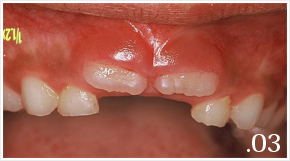

< 症例 > 8歳 女児

前歯の乳歯が抜けてから、1年以上たつが、永久歯が出てこない・・・。母親が心配して、お子様と来院。

歯肉が肥厚し、歯が出てこれない

レーザーにて歯肉の開窓

1週間後 : 歯が出てきました

開窓 1ヶ月後

開窓 1ヶ月半後